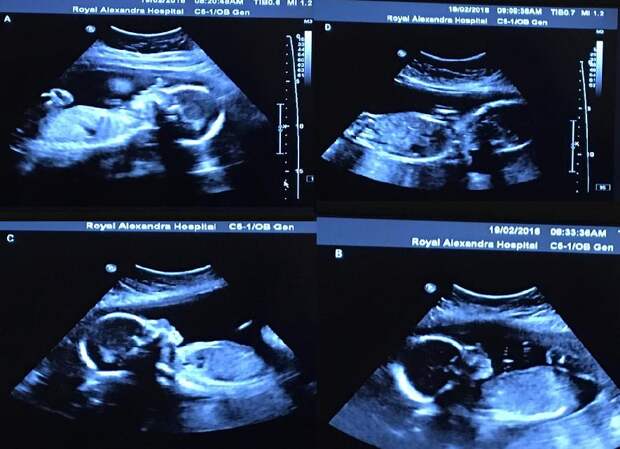

На очередном плановом осмотре гинеколог ошарашил Бетани неожиданным вопросом. Доктор поинтересовался, были ли в роду женщины случаи многоплодных родов. Будущая мама растерялась, а врач тем временем вывел на монитор изображение.

Взглянув на экран, доктор принялся считать…

«Когда он показал на экране третьего младенца, я подумала — хватит! Но медик не умолкал», — вспоминает сегодня многодетная мама Бетани.

Как оказалось, в животе у женщины развивалось четыре плода одновременно. Пара признались, что сначала эта новость заставила их серьезно запаниковать. Но отойдя немного от шока, супруги Вебб начали прикидывать, как им придется изменить свои планы на будущее.